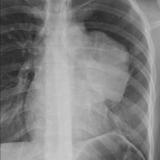

Thymic carcinoma PA